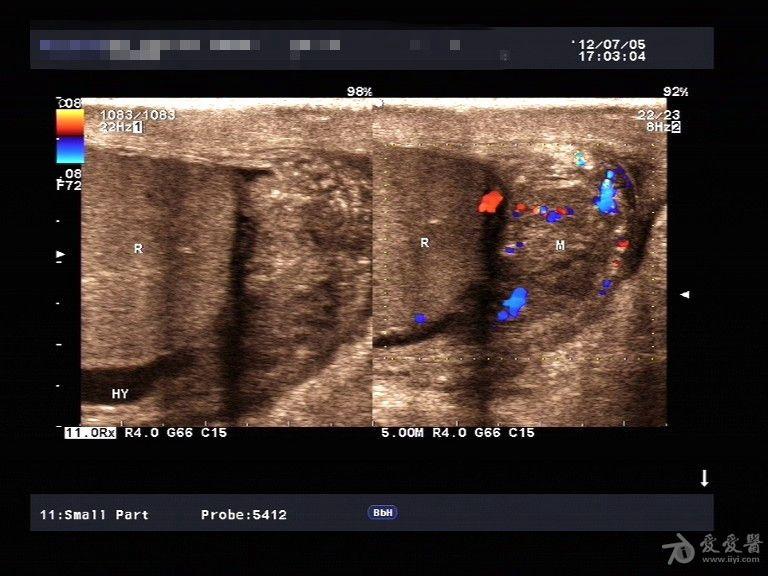

睾丸附睾炎 - 超声医学讨论版 - 爱爱医医学论坛 - 爱爱医医学网

图片尺寸768x576